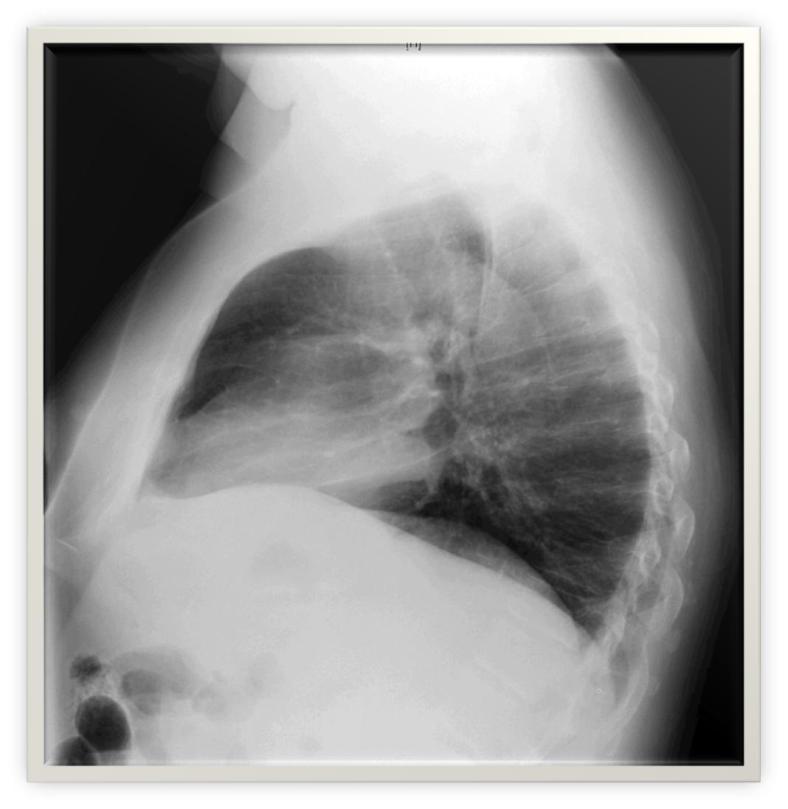

Rx tórax: